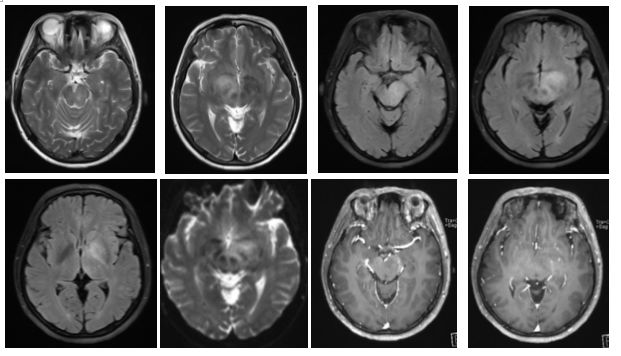

病例2(病例提供: 赵尧辉 老师)

患者,女,18岁。主要症状为急性头痛、呕吐、视物模糊。患者既往有炎症性肠病和口腔溃疡病史。

答案:神经白塞病

本病例开始没有给炎症性肠病和口腔溃疡病史,好多老师考虑是中毒。当一个既往有反复口腔或生殖器溃疡、葡萄膜炎或白塞病其它症状的患者出现神经系统症状时,需要考虑神经白塞病(NBD)。神经白塞病是一种累及多系统的自身免疫性疾病。临床表现为复方性口腔溃疡、生殖器溃疡、皮肤病变和葡萄膜眼,也可累及血管、神经系统、消化道、关节、肺、肾等器官。当累及神经系统时,称为神经白塞病。中枢神经系统受累较多见,可有头痛、Horner综合征、假性球麻痹、癫痫、无菌性脑膜炎、视乳头水肿、偏瘫、失语、截瘫、感觉障碍、精神异常等症状。脑实质NBD典型的好发病灶是脑干,通常累及脑桥,可向上蔓延至中脑、基底节、间脑;可表现为半球的白质病变,也可为半球孤立性病灶,需与肿瘤、脓肿和先天性囊肿等鉴别;急性/亚急性病灶为T1WI上等-低信号,增强通常有强化,T2WI和FLAIR上为高信号,DWI上高信号,相应ADC值降低。